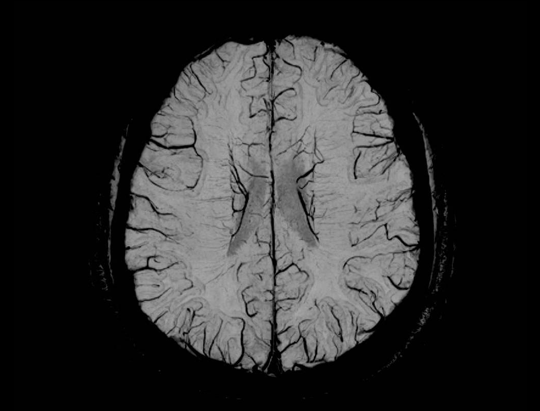

ACS (AI-assisted Compressed Sensing)는 United Imaging의 독점 MR 가속 솔루션으로 속도와 이미지 품질을 최적으로 균형있게 조화시키는 데 사용됩니다. CS, HF, PI를 결합하고 최첨단 딥러닝 신경망을 AI 모듈로 혁신적으로 도입하여 재구성 절차에 적용합니다. 이를 통해 사용자는 영상 품질을 향상시키면서도 검사 시간을 늘리지 않거나 이미지 품질을 저하하지 않고 검사 시간을 단축시킬 수 있습니다. 이는 더 완벽한 검사를 가능하게 하며, 영상의학과 전문의들의 진단가치를 높이고 환자의 편안함을 향상시킵니다.

MRI 영상에서 더 높은 가속 수준을 실현.

각 부위의 획득 시간을 100초 이내로 단축하여, 환자 처리량을 크게 향상시키고 움직임에 인한 아티팩트를 줄입니다.

작은 해부학적 구조물을 더욱 정확하게 묘사하여 진단 능력을 확장시킵니다.

MRI 검사를 견디기 어려워하는 노인, 소아 및 기타 특수 환자들에게 유용하여 검사의 성공률 증대.